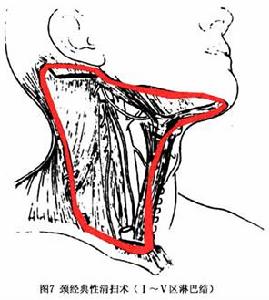

圖7 頸部淋巴結轉移癌已查明原發部位的轉移癌 按原發部位癌治療原則進行治療。原發部位不明的轉移癌,為控制繼發癌的發展, 以延長患者生存期,可以考慮採取積極治療,在治療過程中繼續查找原發灶。

①根據有無淋巴結臨床轉移劃分:頸選擇性清掃術(elective neck dissection):套用於cNO患者,即臨床未發現有轉移轉移淋巴結 但根據原發灶情況(腫瘤部位、 病理分化程度、T分類 以往治療等)來判斷 有較大可能的潛在淋巴結轉移。如口腔癌及聲門上型喉癌,有大約30%患者有潛在的轉移灶。有人主張立即手術頸部。頸治療性清掃術(therapeutic neck dissection):套用於cNl~3患者,即臨床已確定有淋巴結轉移。兩手術範圍均為Ⅰ~Ⅴ區頸全淋巴結清掃。如原發灶為中線器官(喉、下咽、頸段食管、甲狀腺),加用Ⅵ區清掃。

②根據切除組織範圍劃分:頸經典性清掃術(comprehensive neck dissection):切除頸部胸鎖乳突肌 肩胛舌骨肌、頸內外靜脈 頸橫動脈、副神經、頸叢神經等,連同這一解剖範圍內的淋巴結(通常為頜下淋巴結區、頸內靜脈淋巴結上、中、下區,頸後三角淋巴結及鎖骨上淋巴結)全部切除(圖7)。頸改良性清掃術(modified neck dissection):又稱頸功能性清掃術(functional neck dissection),這是20世紀年代以後根據臨床經驗改良經典性清掃,減少手術範圍及手術創傷。保留胸鎖乳突肌 頸內靜脈及脊副神經 適用於淋巴結在3cm以下的N1病例。